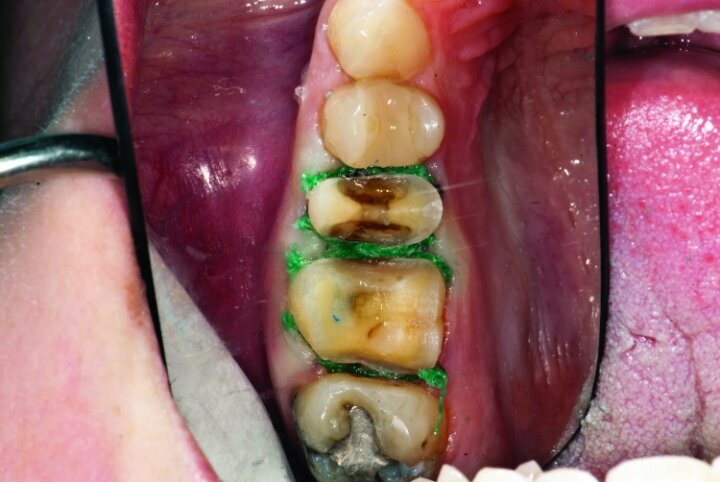

Occlusion was checked with the patient chair at a 45-degree angle. Bausch articulating paper, horseshoe shape, 200 microns thick, was used first, and the patient was instructed to chew on the paper as if chewing gum. Next, the patient was instructed to tap straight up and down on red Troll Foil articulating foil. Any marks from the chewing strokes that weren’t covered by the red paper were removed to eliminate interferences and reduce the risk of material fracture (Figs. 33a–c).

The restorations were then polished (Fig. 34). For #3 e.max restoration, the burs were NTI Cera Glaze—green, blue and yellow, in order. The green prepolisher was not used on the Empress restoration for #4.

The final result was minimally invasive restorations that appear and function naturally, while decreasing risk of tooth fracture, and minimize further risk to the teeth. (Figs. 35a–36b).